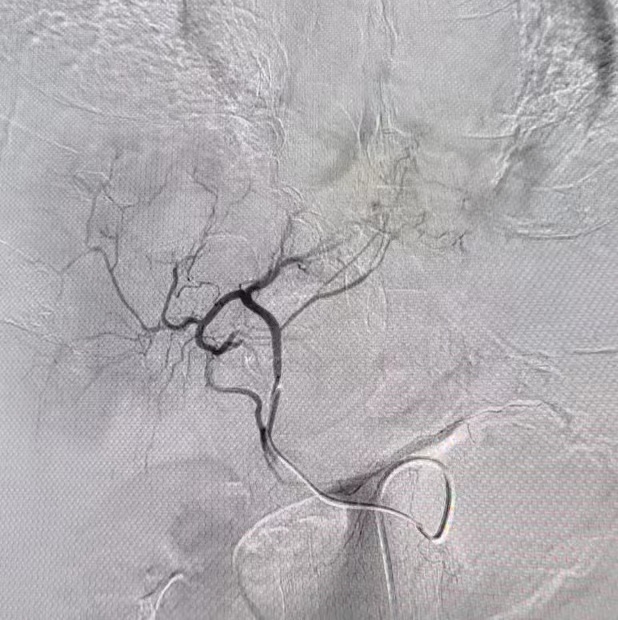

在春节期间,急性腹痛、急性心肌梗死、呼吸衰竭、脑卒中、各种创伤、发热等各类突发性疾病是急诊接诊的主要人群。大年三十,急诊来了一位腹痛患者,接诊医师迅速对患者的病情进行全方位了解,影像学检查报:膈下游离气体,符合消化道穿孔表现,迅速联系急诊外科组医生,协调手术室行剖腹探查手术,术中发现胃底部一处约1cm大小穿孔,周围大量脓液,程三放教授与党旭升医师迅速进行手术修补处理,手术顺利,术后安全返回病房,患者目前恢复良好,近期可以出院。大年初四,一位肝癌破裂出血患者急诊就诊,来院时腹腔大量积血,出现了出血性休克等表现,急需快速止血,我科介入组医师迅速为患者进行了腹腔干动脉、肝动脉造影,发现“犯罪血管”,行肝左动脉栓塞术,稳定了生命体征,考虑患者为肿瘤破裂出血,即使介入栓塞仍有再出血可能,随后我科外科组医师行进一步剖腹手术治疗创造了条件,术程顺利,术后转入急诊ICU病房监护,现患者已脱离生命危险,介入与外科手术的配合,为患者创造最大收益,体现了我科各组间流畅的配合协作,与时间赛跑,为生命健康保驾护航。

急诊介入组医师在行腹腔干动脉、肝动脉造影、肝左动脉栓塞手术